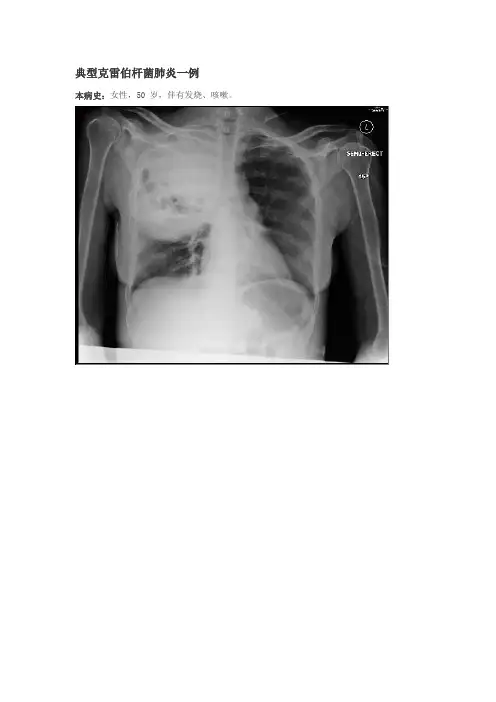

典型克雷伯杆菌肺炎一例本病史:女性,50 岁,伴有发烧、咳嗽。

诊断:克雷伯杆菌肺炎案例要点克雷伯杆菌肺炎是一种细菌感染,通常会阻碍长期嗜酒者和体弱者。

大片实变致使肺叶扩张和裂痕增宽是其特点性影像学表现。

这些表现并非是仅见于克雷伯杆菌肺炎,在其他病因的肺炎也可能会面到。

胸片典型的影像学特点包括大量分泌物引发肺叶实变致使裂隙增宽。

右肺上叶是最多见的发病部位。

尽管裂隙的膨出(叶间裂膨出征)已从来相对用于肺炎克雷伯杆菌肺炎的描述,但不是克雷伯杆菌的特异性病征,而且能够更频繁的出此刻其它病原体引发的肺炎,如肺炎链球菌、流血嗜血杆菌、金黄色葡萄球菌,也能够在原发性肺恶性肿瘤里见到。